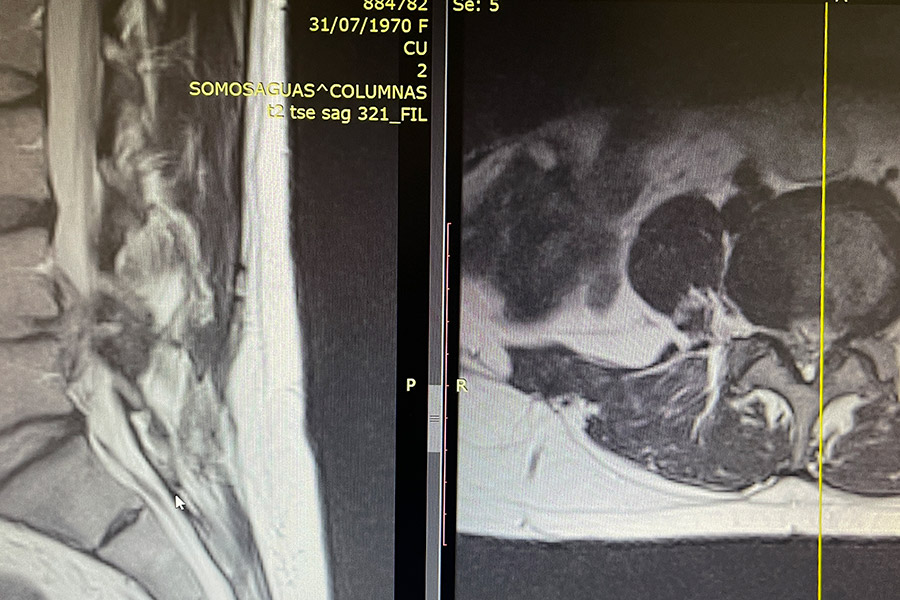

En este caso clínico nos encontramos ante una paciente de 67 años con dolor en la pierna izquierda que le comprime en gran medida las raíces L4, L5 y L5S1.